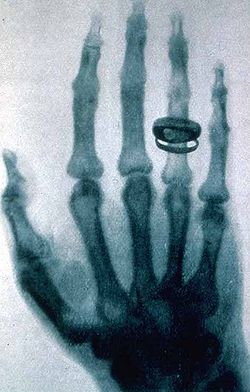

Sin embargo, cuando los beneficios son claros, la percepción del riesgo se encuentra muy disminuida. Por ejemplo el uso de los rayos X en medicina se considerada como segura por la población en general a pesar de un riesgo evidente. Los coches son una de las formas más peligrosas de transporte, pero su utilidad es vista como superior a los riesgos que suponen. Por lo tanto, la percepción del riesgo por parte de la sociedad no puede ser considerada como “científica”.

Primera radiografía publicada por Wilhelm Röntgen en 1896